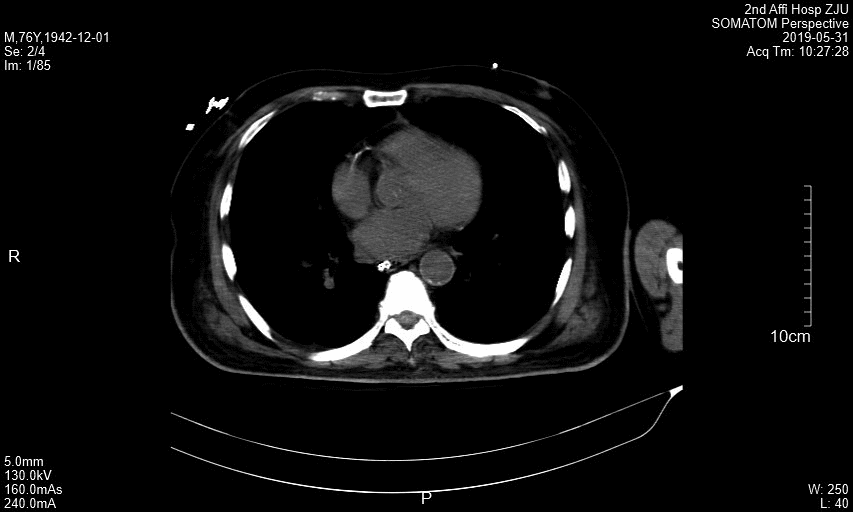

王瑞林_cT层.jpg

附图1  患者横断面CT图